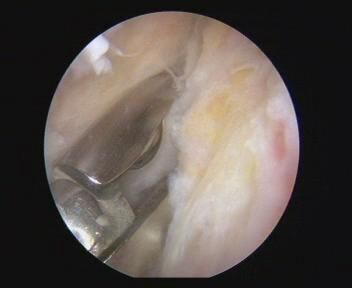

就是瘢痕,所谓瘢痕,不仅是皮肤表面会在创伤后生长,关节内也会有。图中就是粘连松解手术中关节内取出的瘢痕标本。白色,质地坚韧。

小范围的瘢痕可以通过治疗师的手法松开。然而大面积的瘢痕就很难了,有时需要做松解手术。